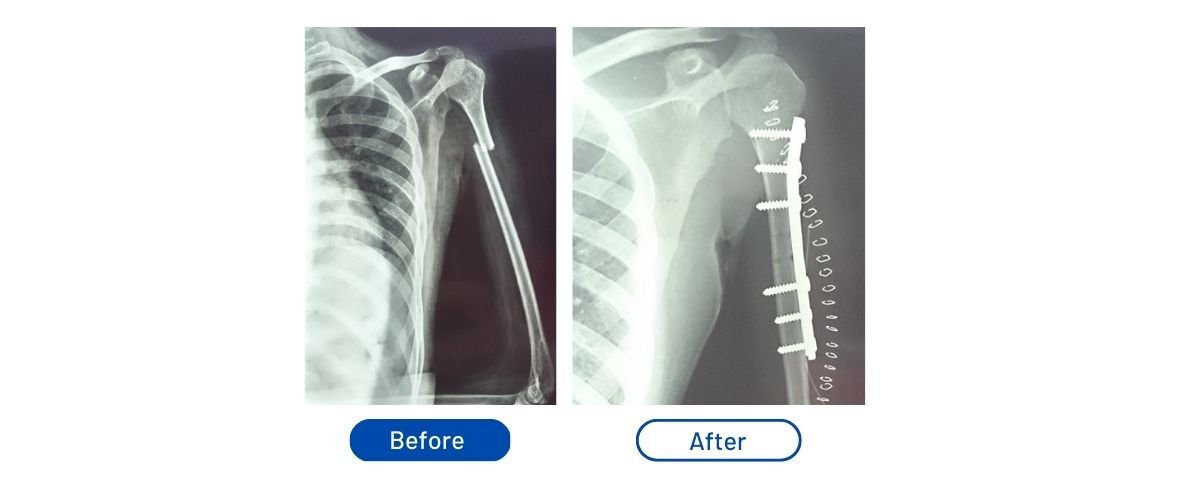

Humerus Fracture